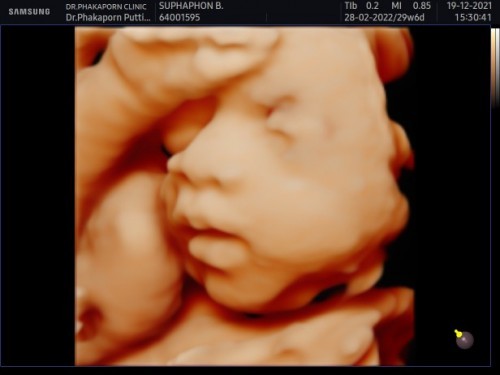

29สัปดาห์กำหนดคลอด เมษาค่ะ หนูเป็น ผญค่ะ💓